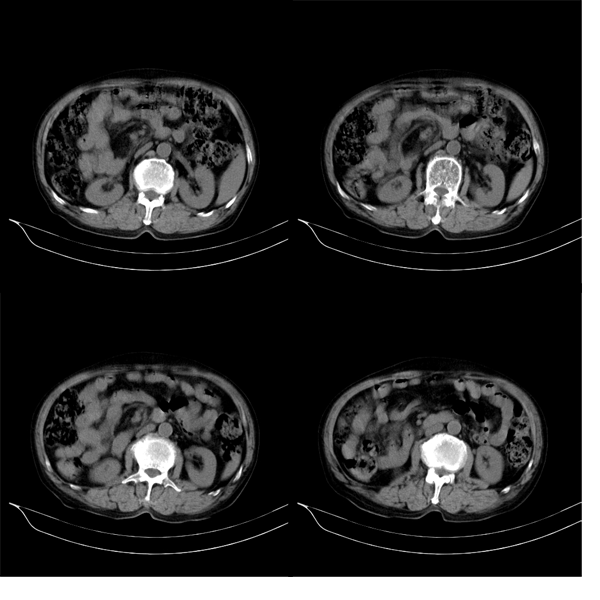

m79y自述30年前做过疝手术,20年前间断出现尿血,每次经抗炎治疗后即好转,近一月来又出现尿血但抗炎后仍尿血.现做双肾+盆腔ct:

双肾10mm扫描

3.双肾平扫未见异常.